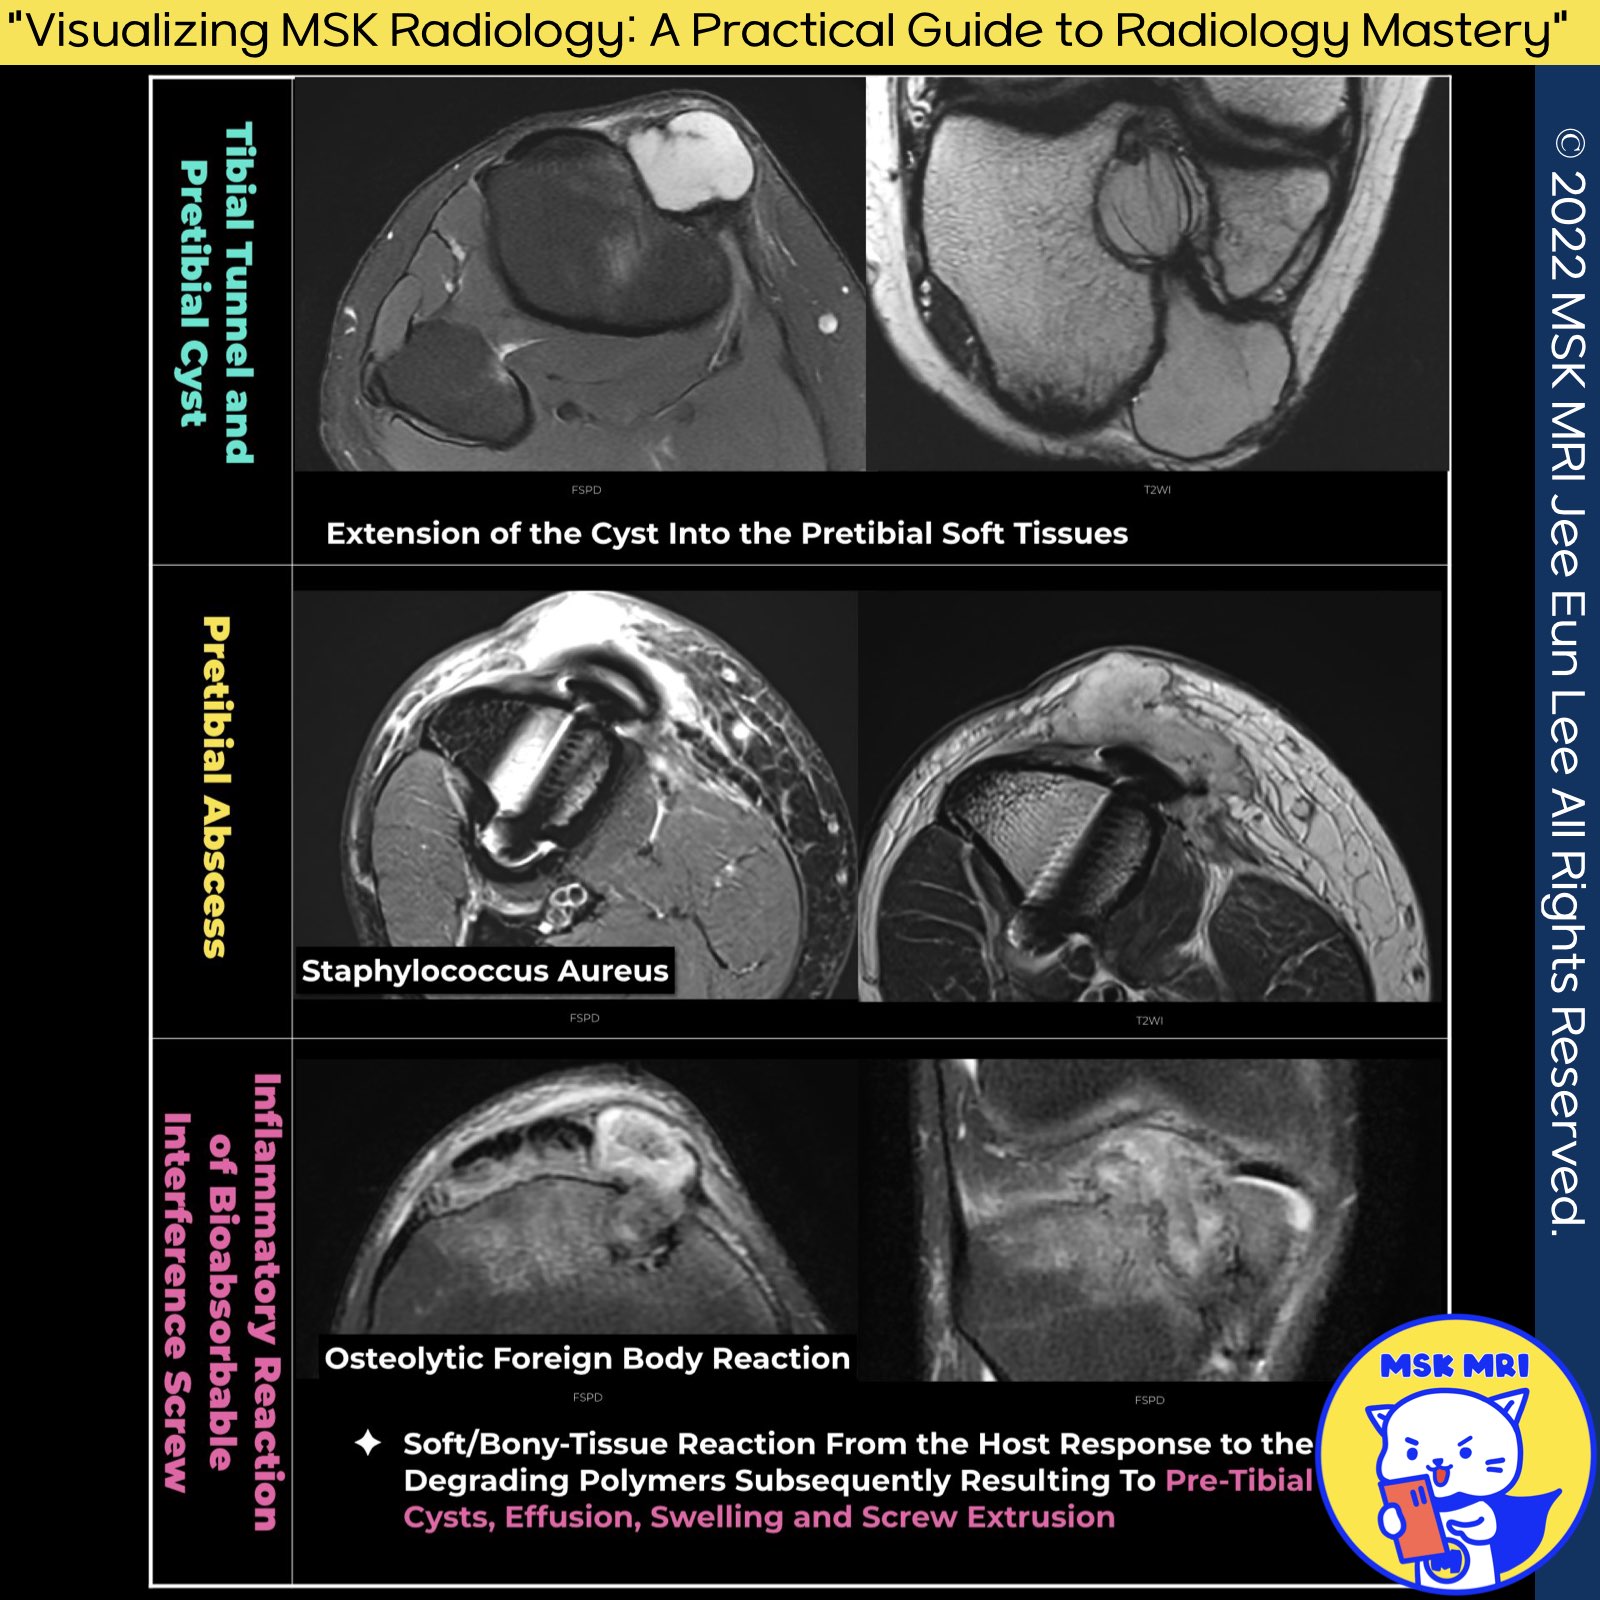

✅Delayed onset bioabsorbable screw reaction

- There are reports of screw-to-soft/bony-tissue reactions from the host response to the degrading polymers.

- This reaction subsequently results in pre-tibial cysts, effusion, swelling, and screw extrusion.

- An index of suspicion regarding those late complications for postoperative anterior cruciate ligament reconstruction patients presenting with local surgical site pain without any constitutional symptoms and normal blood parameters is imperative.